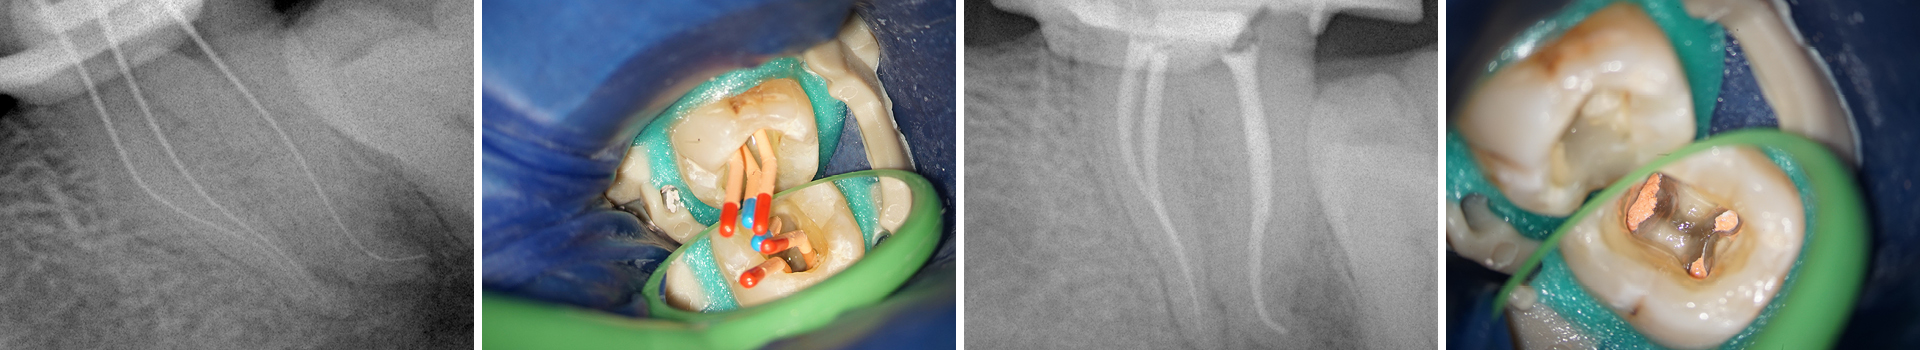

Abbildung 12

Kontrollaufnahme nach Wurzelfüllung: Die Obturation erfolgte in der sog. Single Cone Technik mit einem Sealer auf Tricalciumsilikatbasis. Vergleicht man die Röntgenmess- mit der finalen Obturationsaufnahme, so konnte durch dieses beschriebene Vorgehen sowohl eine signifikante Transportion als auch eine Feilenfraktur vermieden und eine adäquate Obturation ohne Extrusion erzielt werden.

Abbildung 13

Aufnahme vor und nach der Wurzelfüllung; anschließend Applikation des Kompositverschlusses.